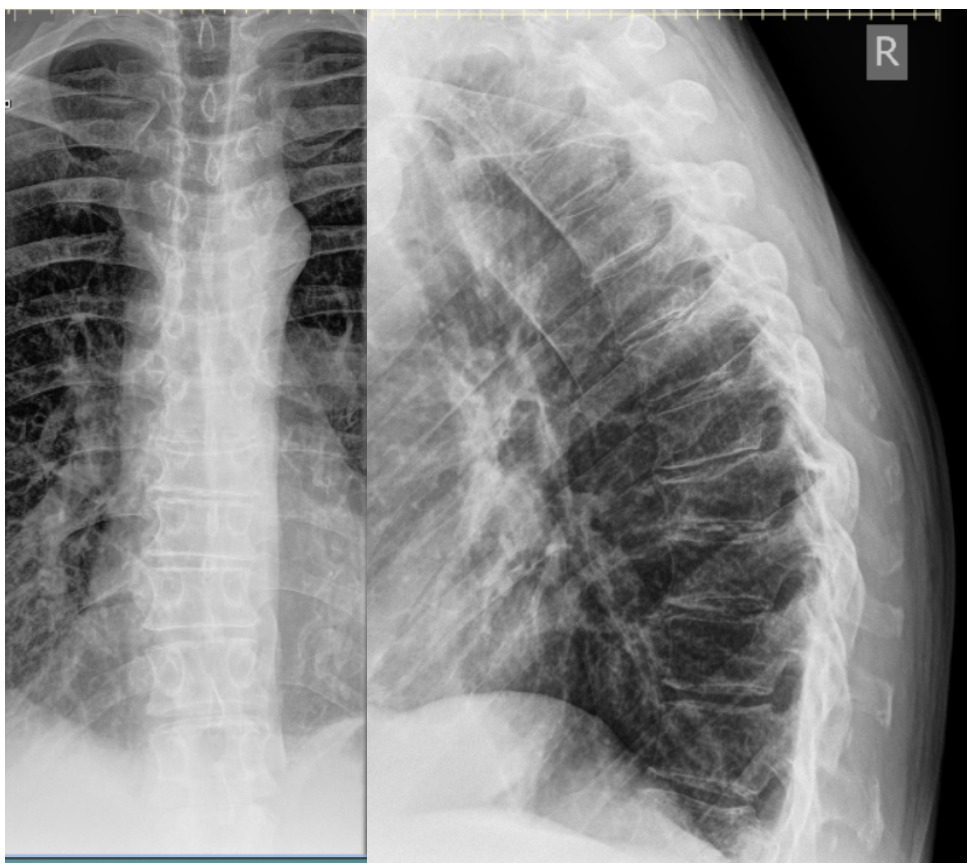

Osteopenia, an old concave compression fracture deformity of the T9 superior endplate, and a well-corticated right T8 rib fracture with callus formation were seen. At this time the patient revealed that he was taking medication for Factor V Leiden, an inherited blood clotting disorder. Chiropractic care using Thompson drops continued and within an additional 4 weeks the thoracic pain resolved.

Chiropractic care using Thompson drops in unaffected spinal regions continued for the next 5 weeks. After a 7-month absence from care, the patient returned reporting midline and centrally worsening non-radiating low back pain after a fall on his back and buttocks approximately 3-4 months prior in his bathroom. He was seen by his medical doctor prior to the treatment visit for this incident and had been referred to physical therapy. He denied head injury, fracture, loss of consciousness, saddle paresthesia or changes with bowel and bladder function. Radiographic examination of the lumbar spine demonstrated superior and inferior endplate fractures of the T12 vertebral body with 60% vertical loss of height not evident on previous examination. Osteoporosis was reported at this time. Examination with CT and MRI were recommended for further characterization of the T12 compression fracture due to the severity of radiographic presentation. The patient was referred to his primary care physician for co-management and the provider was contacted directly due to the loss of vertebral body height (see Table 1 for overview of progression of care).